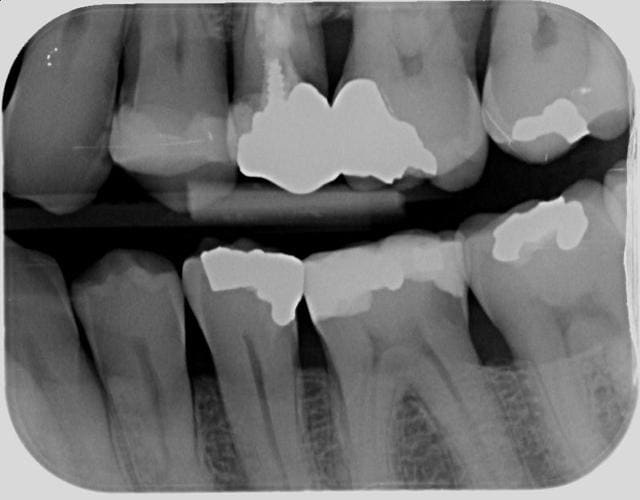

Je compare les btw precedents et tombe sur un hic au niveau de 36 en evolution depuis 2010.

Pour ce que je vois sur les radios, ces soins sont propres, mais pas exceptionnels. Notamment les faces proximales, reconstituées avec des matrices insuffisamment galbées qui produisent un point de contact presque occlusal et qui ne protège pas très bien l'espace inter dentaire en évitant aux aliments de se coincer.

Ceci étant, nous avons tous des patients qui ne passent pas assez les brossettes inter dentaires et déclenchent des caries cervicales incontrôlées.

A stade où nous en sommes, la pulpectomie semble difficile à éviter. Ton patron devrait s'en réjouir, sauf s'il n'est pas payé au pourcentage.

je m'inquiéterais aussi pour la 25.

face distal de 23 également, y a une petite radio clarté.